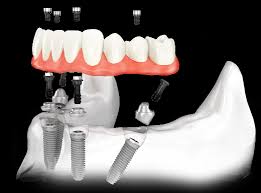

В большинстве случаев всё, что потребуется пациенту, это установка только шести имплантов. Это даст стоматологу возможность поставить несъёмный протез. В таком случае пациент будет чувствовать себя совершенно комфортно — его искусственные зубы будут так же функциональны, как и родные.

Помимо этого, возможна имплантация по другой методике. Используя её, можно поставить несъёмные зубные протезы даже на челюсть, на которой полностью удалены или утрачены зубы. При этом всё, что потребуется сделать, это установить четыре искусственных зуба.